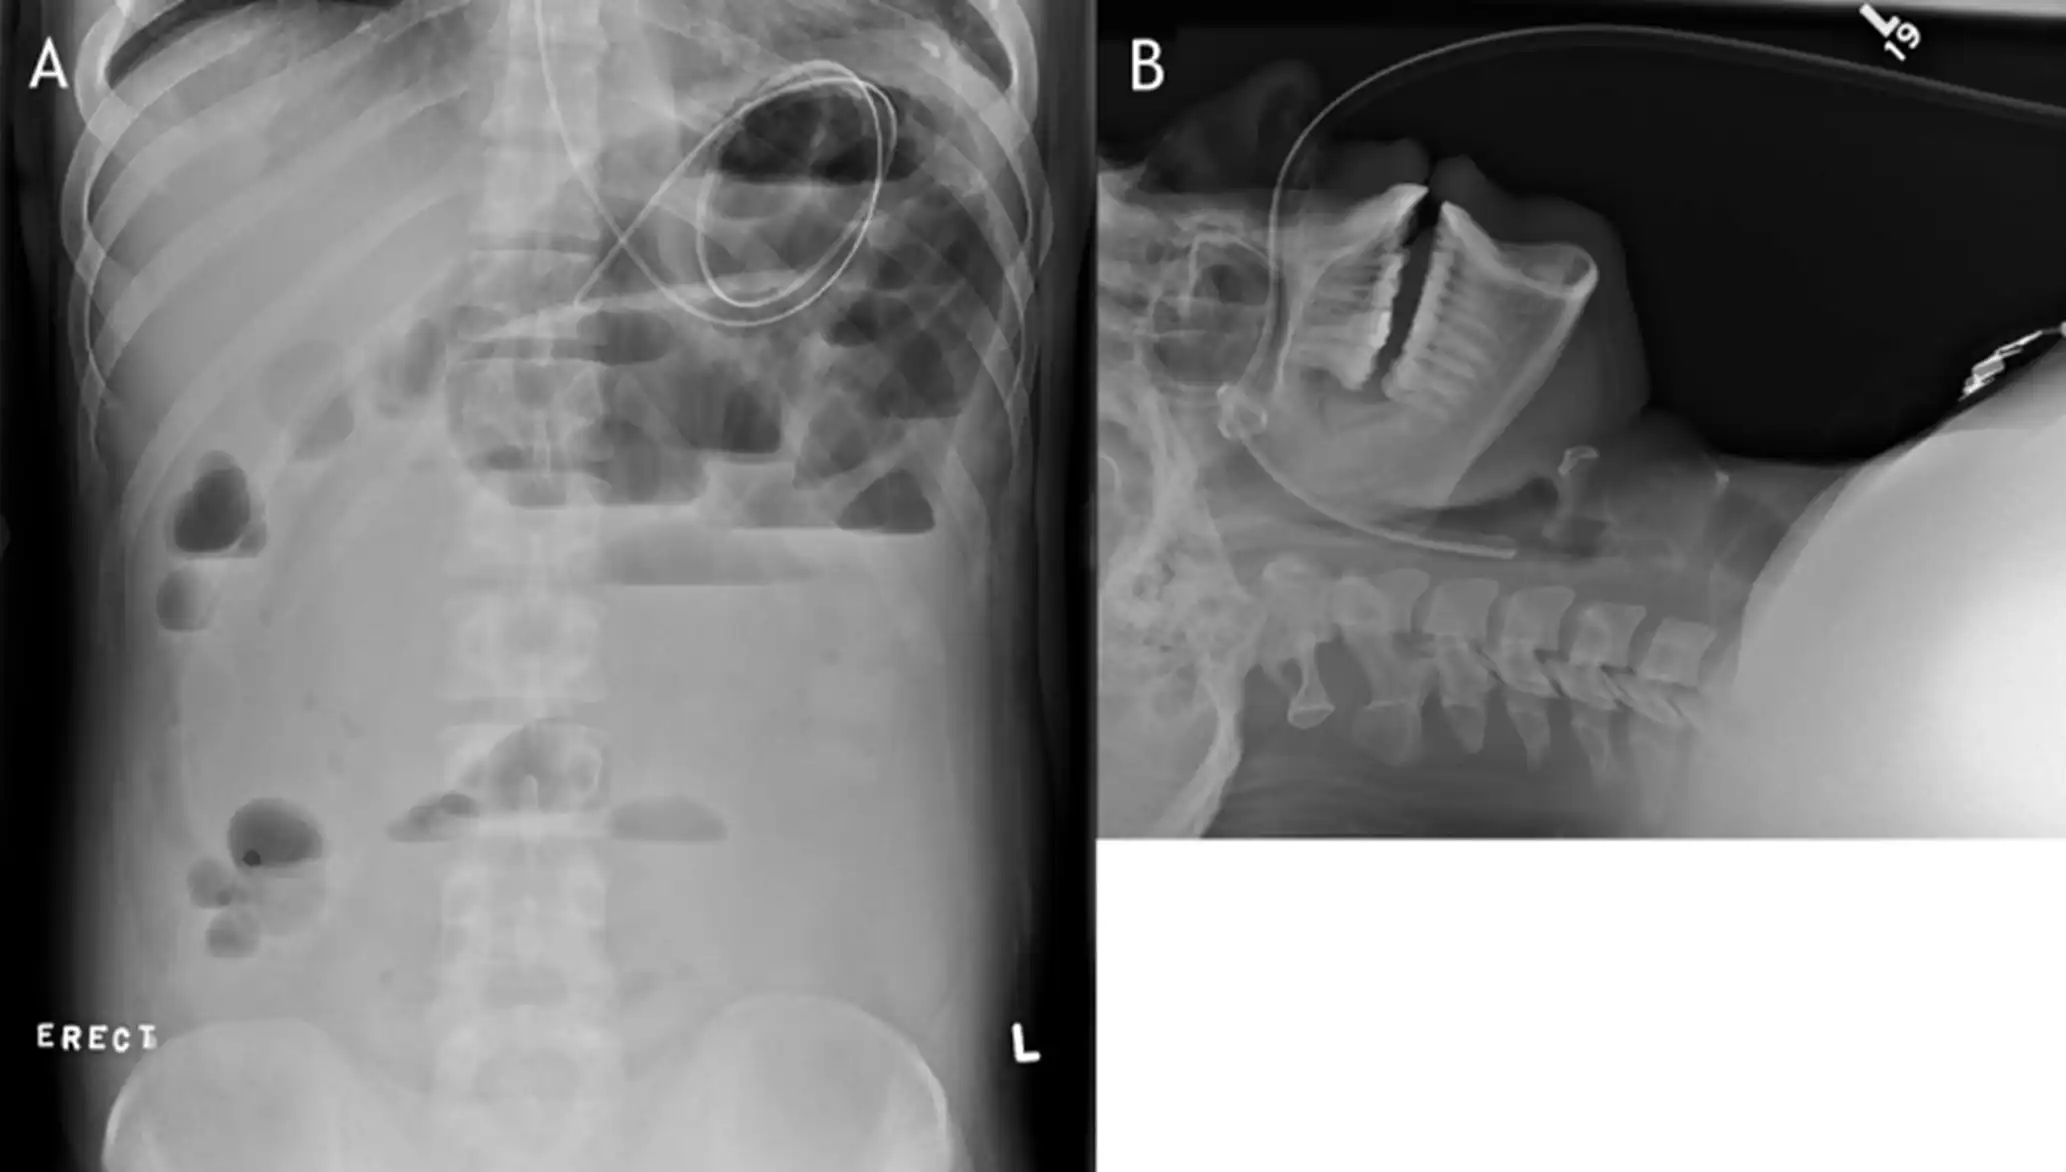

通过国家药品不良反应监测中心及FDA-MAUDE、Pubmed数据库查询到该产品有多起疑似不良事件。经鼻肠营养导管产品在临床中出现的问题主要有:堵管、不通畅;连接处脱落;刻度标记不清、错误;打折、末端开裂;接头断裂/脱落/不匹配;石蜡油润滑管体后刻度标记消失;消化道黏膜损伤;导管拔出困难、拔出过程在患者鼻咽部发生打结等(如图6所示)。

图6 导管打结的X光照片

A.导管在患者体内发生卷曲;B.导管拔出时在鼻咽部打结